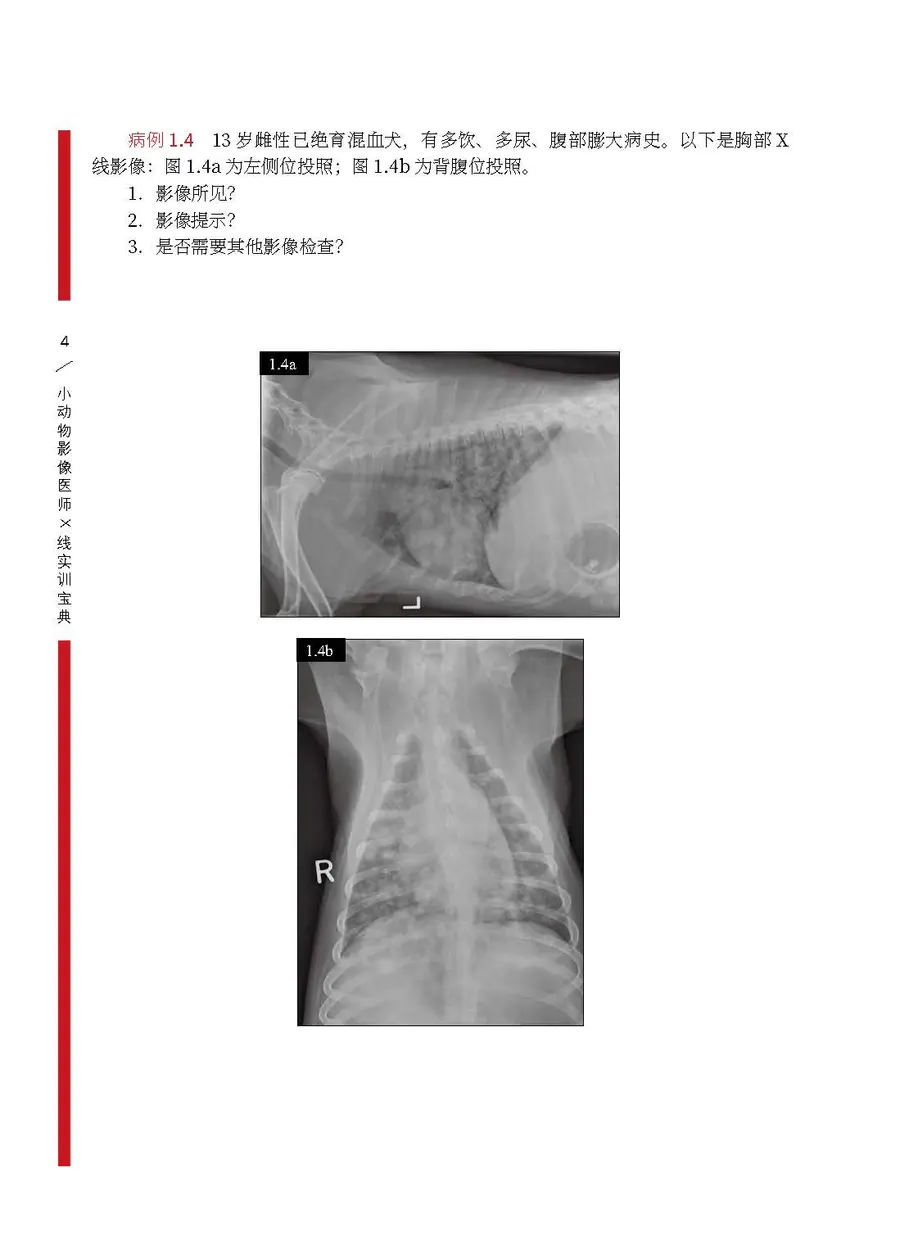

小动物影像医师x线实训宝典

图片尺寸900x1258